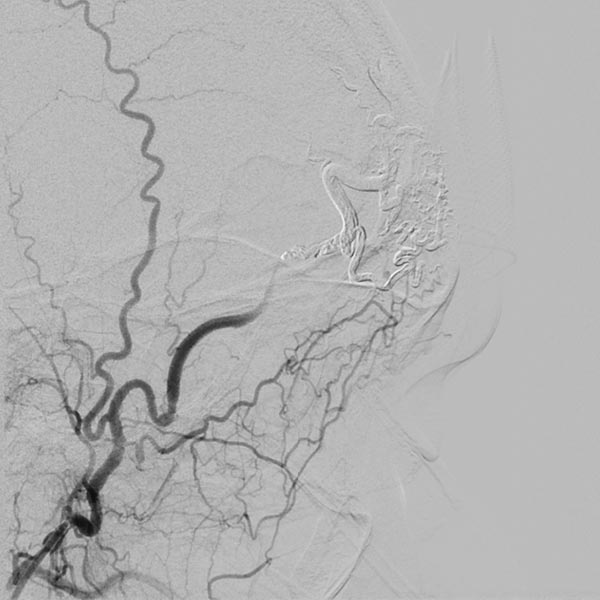

The conventional radiograph (same section as previous image) after completion of the embolization shows the complete cast specimen of the entire nidus with the radiopaque embolization material (cast). This accurately traces the anatomy and angiomorphology of the complete AVM, which is thus occluded.

Completion angiography with contrast injection into the right external carotid artery demonstrates complete occlusion of the nidus of the arteriovenous malformation. On account of the subtraction imaging technique, the cast appears white here (subtracted).

To ensure long-term success and avoid recurrence, as well as to improve the cosmetic result (persistent redness of the skin on the forehead), the complete occluded nidus was resected. To date, the patient has had no recurrence.

Comparison of the initial angiography images and the image of the cast specimen of the AVM completely filled with embolic agent demonstrate the completeness of the occlusion.